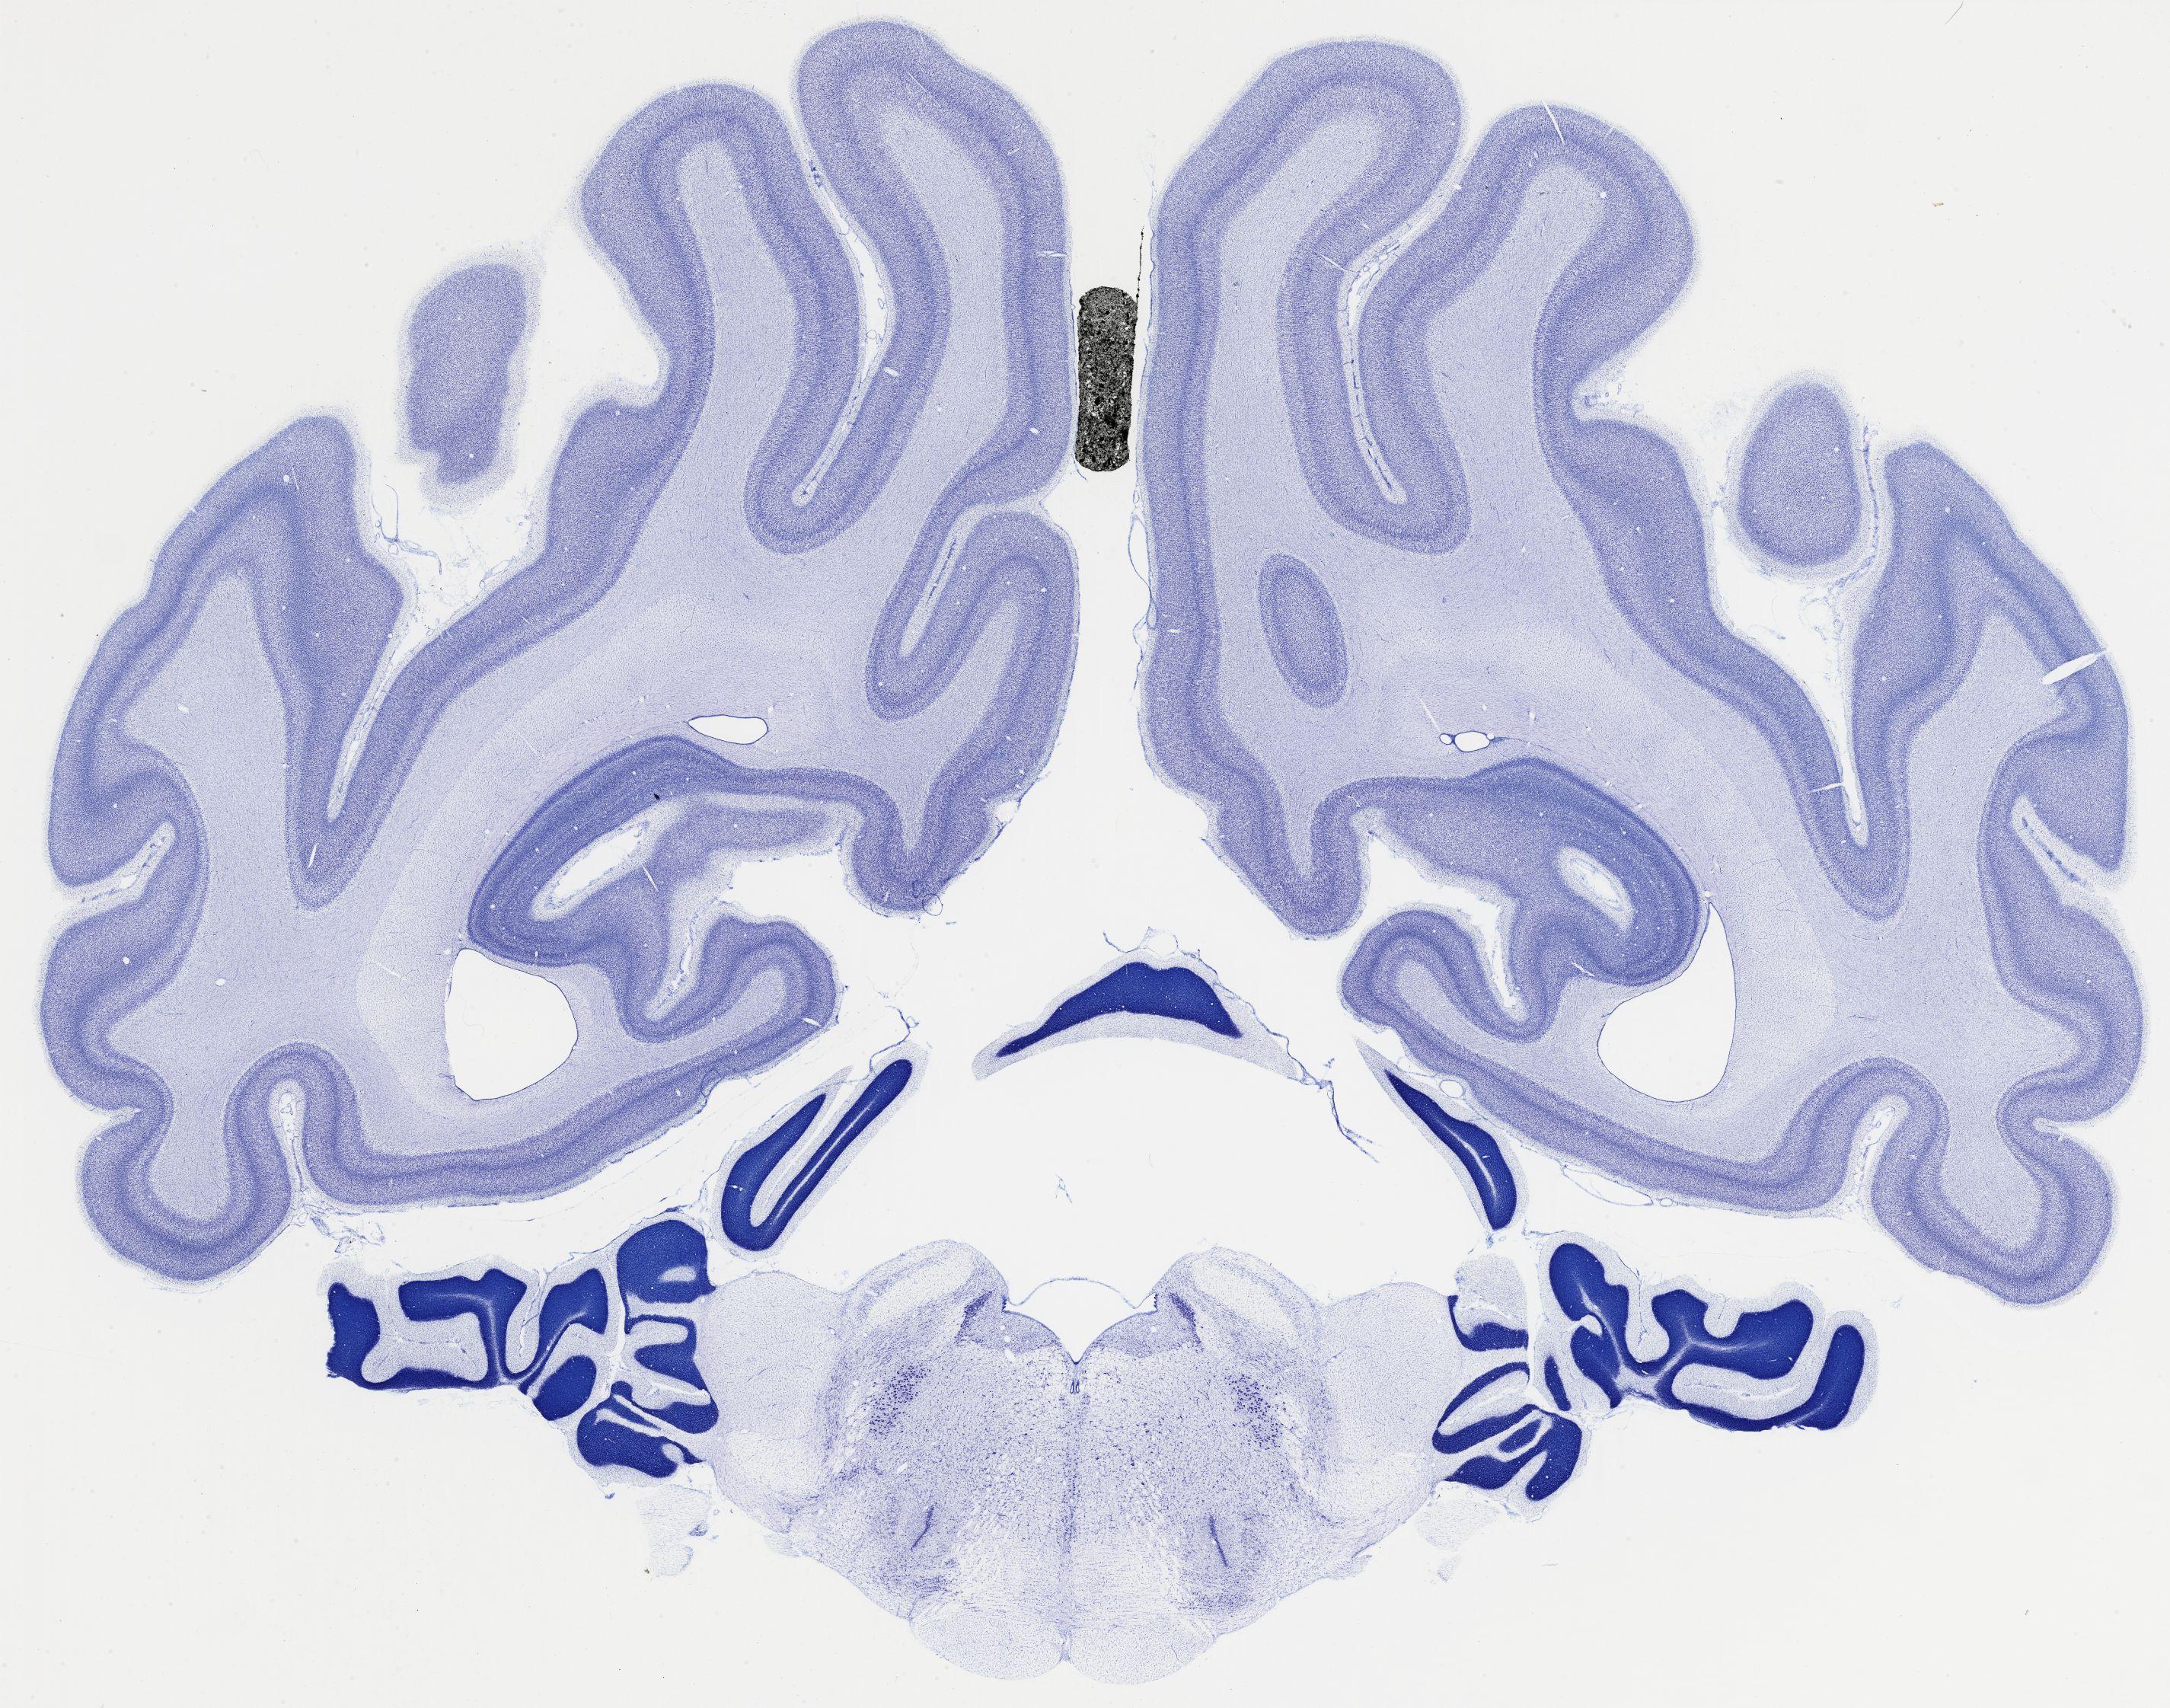

Datasets -> Chlorocebus Aethiops -> Nissl, coronal, histo, Whole-Brain, adult

[ Metadata ]   ·   Source: NeuroScience Associates

thumbnail

524